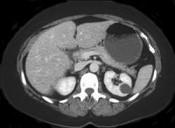

问题 女性,最近感腰部胀痛,体检发现B超右肾正常,左肾有一囊肿,双肾体积不增大,尿常规、肾功能正常,无家族病史,CT表现入图所示,最可能考虑为 ( )

选项 A.肾积水 B.多囊肾 C.多发性肾囊肿 D.肾肿瘤 E.肾结核

答案 C